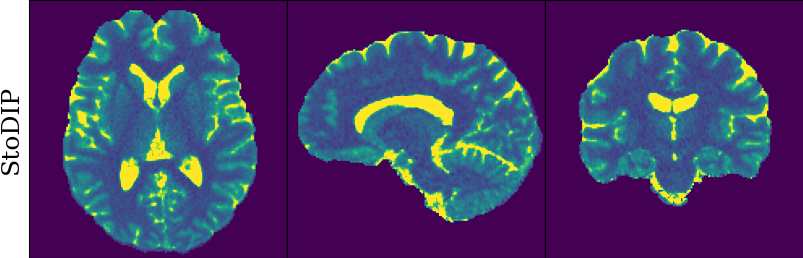

To monitor performance progress, we mapped TSMI to Q-Maps every five epochs. To mitigate the lengthy processing times associated with Dictionary Matching, we implemented a fully connected network to directly map TSMI to Q-Maps [5], significantly reducing processing time. However, for the final assessment, we employed DM on all techniques at the conclusion of the training process (epoch 500). We report in Table 1 the Mean Average Percentage Error (MAPE) of T1/T2 maps, and Peak Signal-to-Noise Ratio (PSNR) and Structural Similarity (SSIM) Index for T1/T2 and normalised PD. To accompany these metrics we also offer in Fig. 2 the reconstructed T1 and T2 maps for the different approaches.

The training and validation loss (Fig. 1) served as valuable guides for architecture and training design. To demonstrate this, we selected a subset of experiments in which we kept certain variables fixed and only modified the one under inspection. From Fig. 1 (a)-(d), MAPEs curves show there is a clear setting with the preferred performance. Specifically, from Fig. 1a, it is evident that using DRUNet yields a clear improvement over the original architecture. This could be attributed to the utilisation of residual units in addition to other architecture differences, such as the choice of upsampling operator (transpose convolution for DRUNet and trilinear for DIP). The choice of input (Fig. 1b) demonstrated a consistent pattern among the tested options, with low rank (conjugate gradient) initialiser marginally outperforming the others. Fig. 1cshows that by epoch 100, stochastic approaches exhibit lower reconstruction errors compared to non-stochastic methods. For example, adaptive LR with stochastic training yields a combined MAPE of 61.40% (17.09% T1 and 44.31% T2) vs. 213.69% (35.50% T1 and 178.19% T2) for the non-stochastic method. This fast convergence is due to adaptive LR and stochastic updates across coils. Despite similar execution times ( 34 min for stochastic with adaptive LR vs. 32 min for non-stochastic with fixed LR), the rapid error reduction makes StoDIP more attractive for training.. To assess the early stopping of DIP models, a key element, we present Fig. 1d. The original work by Ulyanov et al. [21] used 2k iterations, while Hamilton et al. [12] used 30k. In contrast, our settings show StoDIP achieving competitive performance in under 500 epochs (4k iterations) on the entire volume. However, StoDIP can overfit to k-space measurements, affecting reconstruction accuracy, and thus the iteration at which it stops could have a greater impact. We show that adding a spatial penalty term addresses overfitting and instabilities. This is supported by the maps in Fig.2, supplementary material Figures 1-3, and metrics in Table 1. StoDIP reconstructions lack aliasing artifacts, and the TV regularizer (StoDIP + TV) further improves Q-Map reconstruction by reducing checkerboard artifacts observed in StoDIP outputs alone.